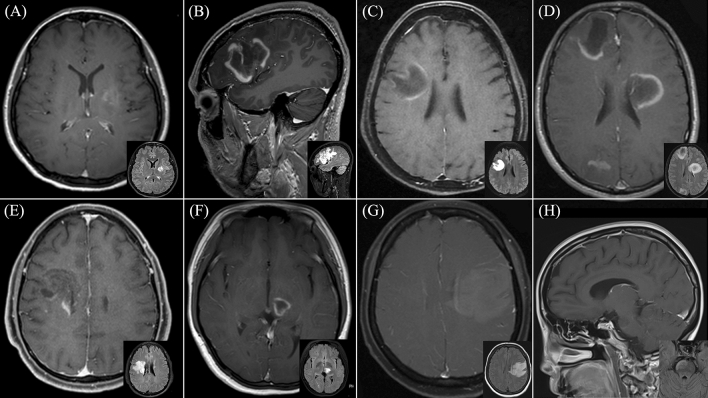

All TDL in the study demonstrated gadolinium enhancement, with open ring enhancement observed in half of the patients (50%). Upon reviewing diffusion-weighted imaging sequences, peripheral restricted diffusion, in which the area of restricted diffusion was at the lesion border, was observed in twenty-one patients (87.5%). Remarkably, we observed that the restricted diffusion area at the lesion border was typically the same area that showed gadolinium enhancement. Only 8.3% did not display restricted diffusion. Additionally, 80.8% exhibited mild perilesional edema, while 76.9% had a mild mass effect. T2W hypointense rims and the central vein sign were observed in approximately half of the patients (45% and 56.5%, respectively). Besides, brain MRI of ten patients revealed the presence of co-existing demyelinating lesions in various brain regions. Representative brain MRI from six patients within the study cohort is illustrated in Fig. 4. Representative brain MRI demonstrating the central vein sign (CVS) and the T2-weighted hypointense rim, is revealed in Fig. 5.

Figure 4.

Representative brain magnetic resonance imaging (MRI) in six patients diagnosed with tumefactive demyelinating lesions (TDL). Post-gadolinium T1-weighted imaging is displayed in the larger picture, with a smaller Fluid-Attenuated Inversion Recovery (FLAIR) MRI provided in the lower right corner. (A) Patient 1: Heterogeneous enhancing pattern of the left basal ganglia lesion. (B) Patient 2: Open ring pattern of the left frontotemporal lesion. (C) Patient 12: Open ring pattern of the right frontoparietal lesion. (D) Patient 17: Open ring pattern of three lesions at the right frontal, left frontoparietal, right parietooccipital region. (E) Patient 20: Heterogeneous enhancing pattern of the right frontal lesion with Balo-like appearance. (F) Patient 22: Open ring pattern of the left thalamic lesion. (G) Patient 23: Patchy enhancing pattern of the left frontoparietal lesion. (H) Patient 25: Open ring pattern of the right-sided pontine lesion.